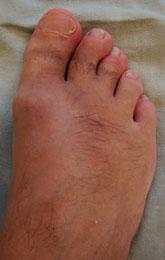

- На поздних стадиях — заметная деформация суставов, которая становится очевидной при осмотре.

- Отечность в области основания большого пальца, покраснение.

На третьей степени боли становятся постоянными и беспокоят даже в состоянии покоя. Тыльное сгибание пальца отсутствует, подошвенное ограничено. Возникает деформация сустава. На рентгенографических изображениях фиксируются костные наросты, выраженная деформация суставных поверхностей.